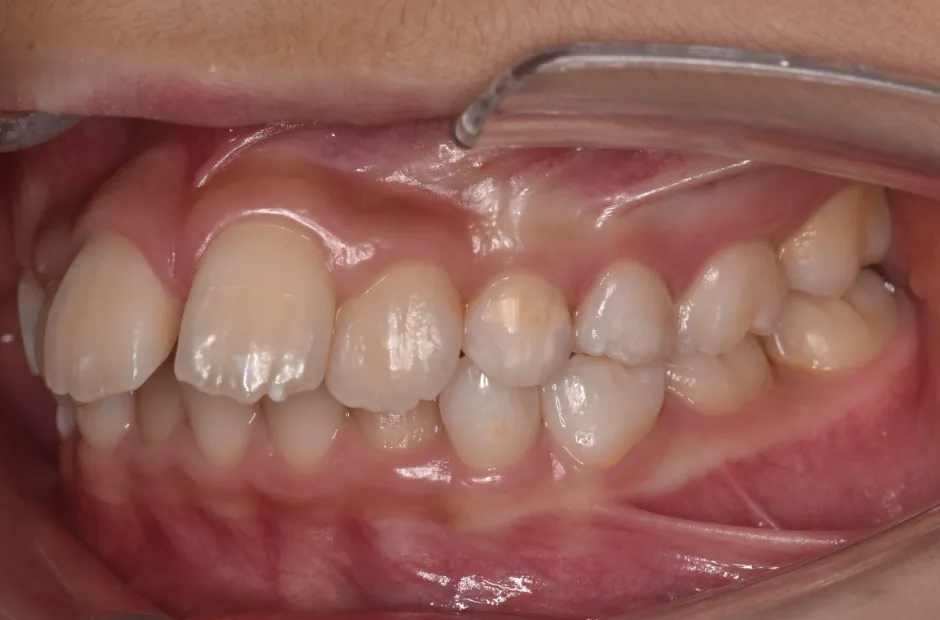

拡大床装置

叢生

| 診断名・主訴 | 叢生 |

|---|---|

| 年齢・性別 | 10歳・女性 |

| 治療期間・回数 | 2年半 |

| 治療に用いた主な装置 | 拡大床装置 |

| 抜歯部位 | なし |

| 治療費 | 30万円(税抜) |

| リスク・副作用 | 装置による違和感・疼痛・歯肉退縮・歯根吸収・虫歯のリスクなど |

治療前

治療中

治療後